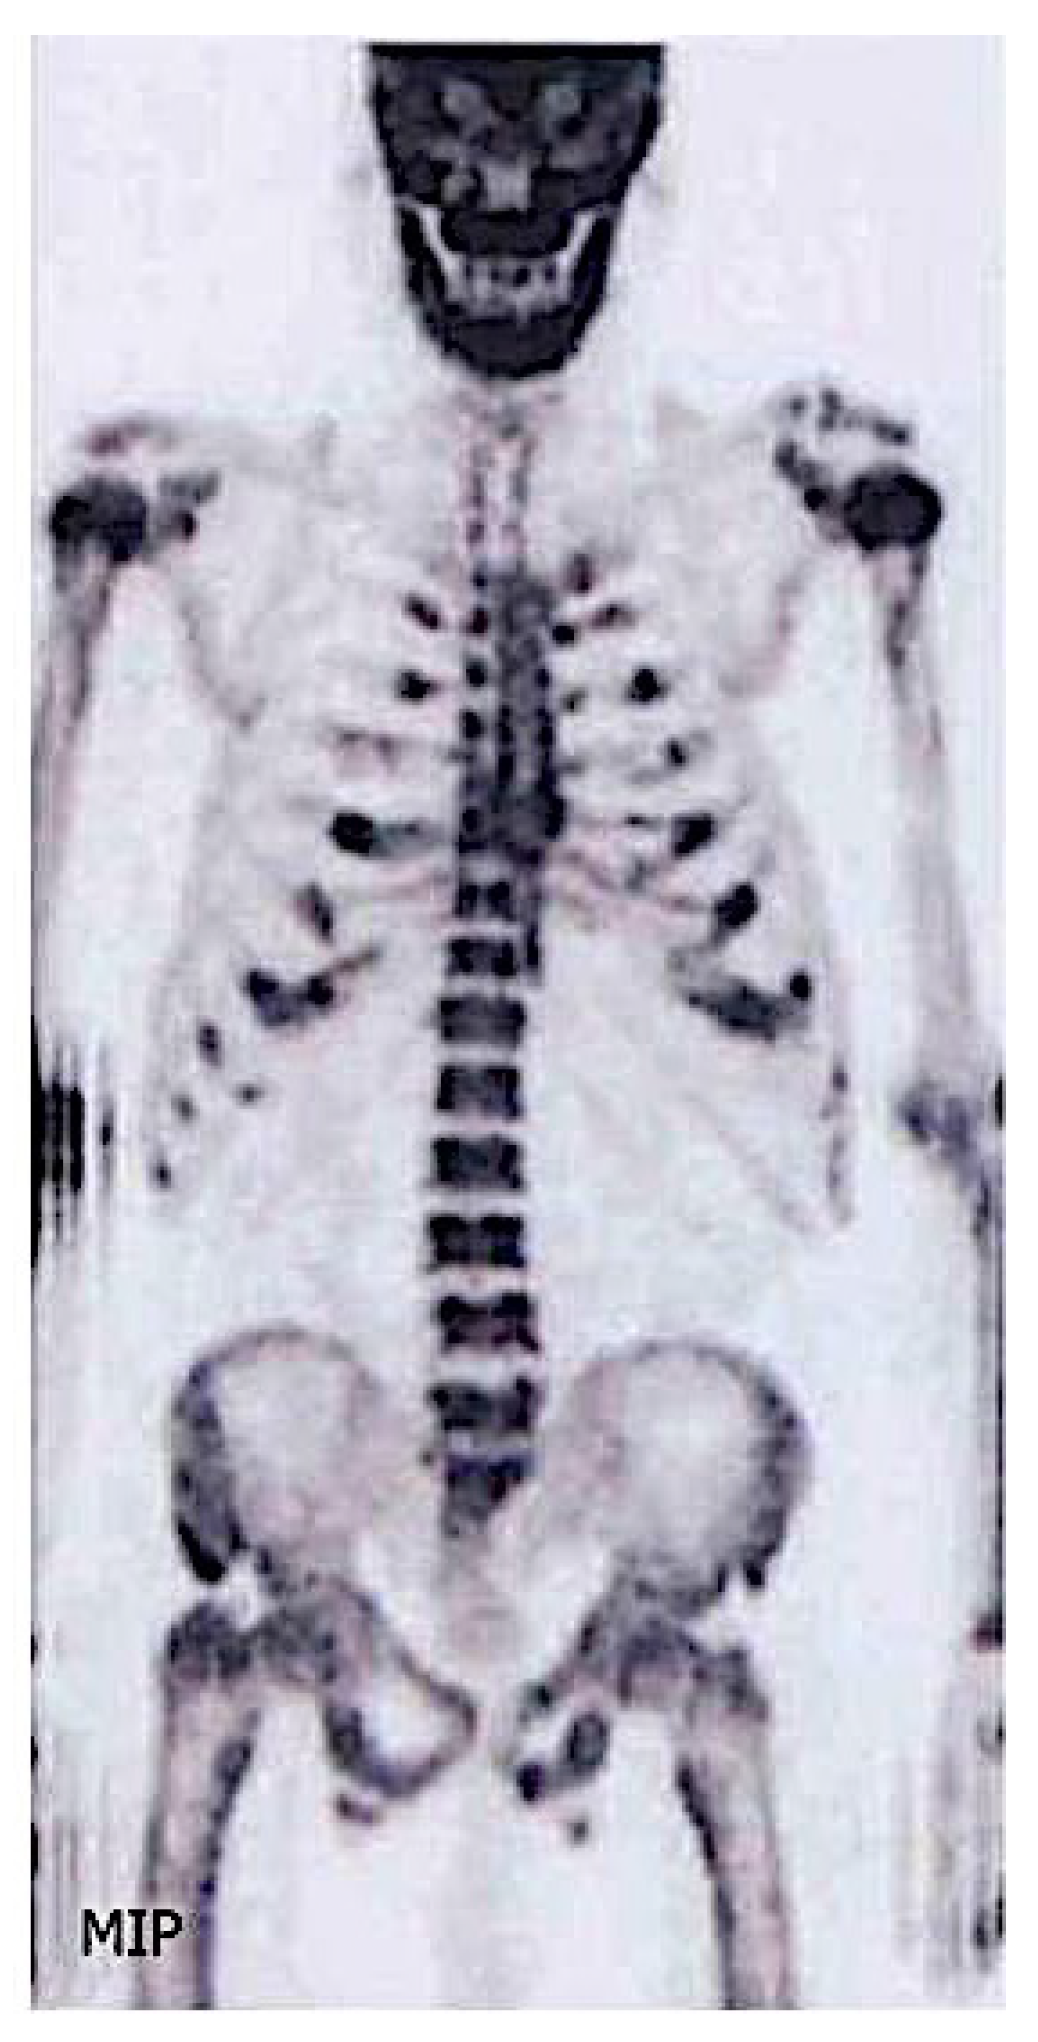

3.8. Other Imaging Techniques

- Van den Wyngaert, T.; Strobel, K.; Kampen, W.U.; Kuwert, T.; van der Bruggen, W.; Mohan, H.K.; Gnanasegaran, G.; Delgado-Bolton, R.; Weber, W.A.; Beheshti, M.; et al. The EANM practice guidelines for bone scintigraphy. Eur. J. Nucl. Med. Mol. Imaging 2016, 43, 1723–1738. [Google Scholar] [CrossRef]

- Abdelrazek, S.; Szumowski, P.; Rogowski, F.; Kociura-Sawicka, A.; Mojsak, M.; Szorc, M. Bone scan in metabolic bone diseases. Review. Nucl. Med. Rev. 2012, 15, 124–131. [Google Scholar]

- Aaltonen, L.; Koivuviita, N.; Seppänen, M.; Tong, X.; Kröger, H.; Löyttyniemi, E.; Metsärinne, K. Correlation between 18F-Sodium Fluoride positron emission tomography and bone histomorphometry in dialysis patients. Bone 2020, 134, 115267. [Google Scholar] [CrossRef] [PubMed]

- Messa, C.; Goodman, W.G.; Hoh, C.K.; Choi, Y.; Nissenson, A.R.; Salusky, I.B.; Phelps, M.E.; Hawkins, R.A. Bone metabolic activity measured with positron emission tomography and [18F]fluoride ion in renal osteodystrophy: Correlation with bone histomorphometry. J. Clin. Endocrinol. Metab. 1993, 77, 949–955. [Google Scholar] [CrossRef] [PubMed]

| Bone Scintigraphy | Tracer accumulation occurs in osteoblastic activity, and to a lesser extent, skeletal vascularity; Systemic amyloid burden; | Whole body | Osteoarthritis Metabolic Bone Disease: -Hyperparathyroidism and vitamin D deficiency -Osteomalacia; Fractures Enthesopathies Osteonecrosis Rare Osteoarticular Diseases: Sarcoidosis with bone involvement; Amyloidosis: 123I SAP scintigraphy if available—assess amyloid deposition in liver, spleen, kidneys, adrenals, localized soft tissue deposits and bones 131I-β2M amyloidosis | 3–5 |

| PET | Bone formation rate, osteoclast, osteoblast, erosion and mineralized surfaces | Lumbar region | Low or high bone turnover disease | All |